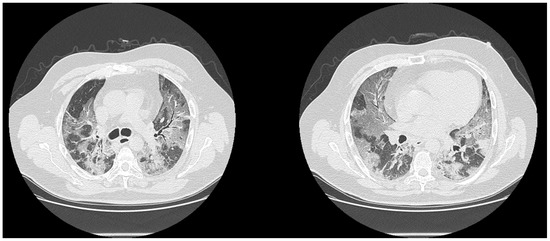

| CT diagnosis at second CT reading | |||||

| Positive | 292 | 97.3 | 36 | 46.2 | <<0.001 |

| Negative | 8 | 2.7 | 42 | 53.8 | |

| High diagnostic confidence level | Bilateral multifocal GGO with predominantly peripheral distribution associated or not with septal thickening (crazy paving) and/or consolidations; multifocal GGO of rounded morphology associated or not with crazy paving and/or consolidations; multifocal GGO associated with findings of organizing pneumonia. |

| Intermediate diagnostic confidence level | GGO with diffuse distribution associated or not with crazy paving and/or consolidations; bilateral multifocal GGO and/or consolidations without a prevalent peripheral distribution and without rounded morphology; unilateral GGO with or without consolidation. |

| Low diagnostic confidence level | Isolated small areas of GGO and/or consolidations with non-rounded morphology were included in the low confidence level. |